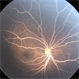

- Lipemia Retinalis

- Retcam 3

- FA of 2-month-old female patient diagnosed with lipemia retinalis.